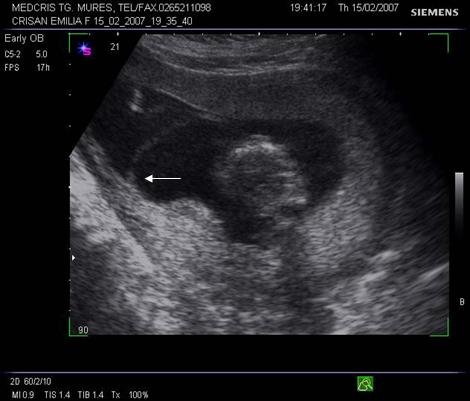

Fig nr 37. Aceeasi sarcina gemelara de 6 sapt., sectiune fara embrioni,cu sacii amniotici caracteristic dispusi in ochi de bufnita